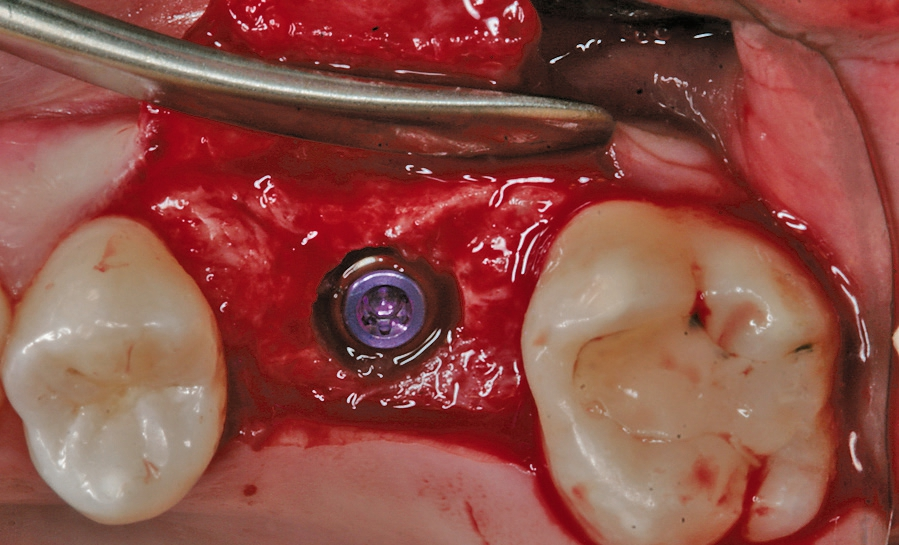

Eine der häufigsten Indikationen für Implantate überhaupt stellt die Einzelzahnlücke nach Verlust eines ersten Molaren dar. Bei den meisten Fällen liegt ein stabiles vertikales Knochenangebot an den Nachbarzähne vor, sodass in der Regel nach Ausheilung des apikalen Granulationsgewebes von einer guten Knochenregeneration auszugehen ist, so dass keine Notwendigkeit der Insertion von kurzen oder ultrakurzen Implantaten gegeben ist. Im Oberkiefer kann bei einer weiten Divergenz der Wurzeln des extrahierten Zahnes es zu einer ausgeprägten Pneumatisation der Kieferhöhle kommen. Daher werden gerade beim jugendlichen Patienten dort dann kurze Implantate eingesetzt, um auf eine Sinusbodenelevation mit einem lateralen Zugang verzichten zu können [3]. Die Implantate können mit oder ohne eine Navigationsschablone gesetzt werden [4]. Da die Lücke begrenzende Nachbarzähne eine gute Orientierung in der mesio-distalen Dimension ermöglichen, kann oftmals auch auf eine Orientierungsschablone verzichtet werden. In der oro-vestibulären Richtung muss der Anwendung des größeren Durchmessers Rechnung getragen werden. Dies kann mit einfachen Positionierungshilfen erfolgen, damit die Implantatachse möglichst zentral in der Kaufläche zu liegen kommt (Abb. 1-8). Die Einzelzahnlücke kann mit einer integrierten verschraubbaren Abutment-Hybrid-Krone oder mit einem Abutment und einer zementierten Krone versorgt werden [5].